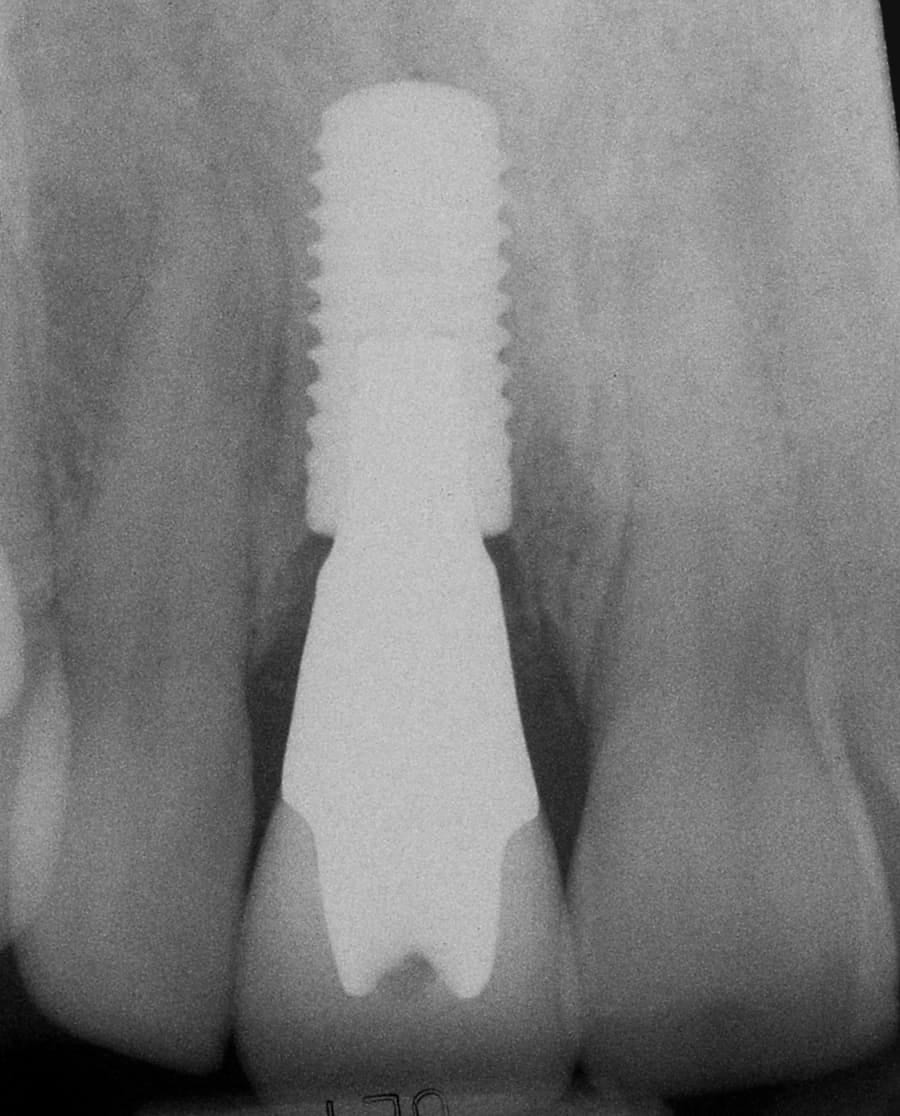

After: Single, all-ceramic crown attached to an all-ceramic, CAD-CAM designed and generated abutment (implant post). A delayed treatment approach was undertaken: tooth/root removal and grafting; 4 months healing; interim removable partial tooth replacement; implant placement; 6 months healing; proto-type (transitional fixed) implant crown, then the definitive implant restoration. The new tooth blends in perfectly with the natural, adjacent teeth.